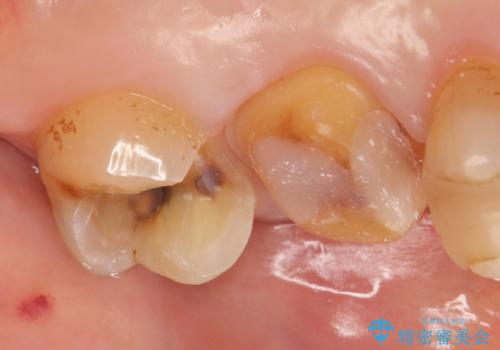

- 左上6番目の歯が欠けてしまったので診て欲しいといらっしゃった方の症例です。

左上6番目は銀歯・虫歯を除去後、オールセラミッククラウンにて補綴を行いました。

左上7番目も虫歯だったため、銀歯・虫歯を除去後、セラミックインレーにて修復を行いました。